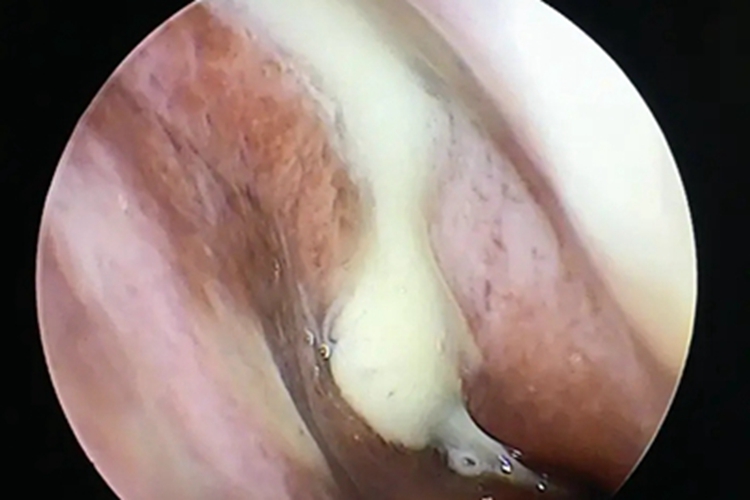

急性化脓性鼻窦炎可出现鼻腔黏膜肿胀,内有大量脓性或黏脓性鼻涕,鼻涕为黄色或黄绿色黏稠样,偶可带有少许血液,难以擤尽,也不易从鼻腔流出,可向后流至咽部,伴有咽痒、恶心等症状。